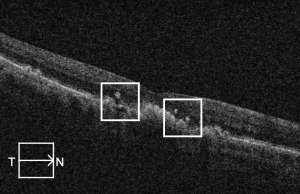

Drusen ooze

The term "drusen ooze" describes the seepage of drusenoid material from the RPE into the outer retinal layers due to RPE dysfunction or collapse.[24] This seepage material appears hyperreflective on OCT and may be associated with RPE thinning, PED collapse, or ellipsoid zone disruption. Drusen ooze is considered a structural biomarker in intermediate to advanced nonexudative AMD, and it has been reported to have a prevalence of 41%-65% in patients with dry AMD.[25][26]

Three imaging patterns of drusen ooze have been described, helping to distinguish this finding from other hyperreflective abnormalities on OCT:

- Increased RPE reflectivity above a druse, appearing brighter than the adjacent, normally apposed RPE overlying the Bruch membrane.

- Discrete hyperreflective foci at the RPE level (hyperreflective dots, HRDs), visually similar in brightness to the elevated RPE but not physically continuous with the RPE layer.

- Intermediate-reflectivity dots within the outer nuclear or plexiform layers that are more reflective than the surrounding retina but less so than the hyperreflective foci. These are typically associated with localized disruptions in the RPE.[26]

Oozing may occur subtly, as a slow leak, or more dramatically as a “volcano-like” eruption from within the druse. The term “vent” has been used to describe hyperreflective foci migrating through the Henle fiber layer. corresponding histologically to migrating RPE cells and RPE debris. The features of drusen ooze are important to recognize, as misclassification as CNV may lead to overtreatment with anti-VEGF injections.

Drusen ooze has been suggested to be a biomarker indicative of AMD progression. Monés and colleagues (2017) evaluated 48 eyes of 33 patients with AMD and soft drusen, finding collapse of 1 or more drusen occurring in 39.6% over ≥18 month follow-up. Of the foci of collapsed drusen examined, 91.2% were associated with RPE hyperreflectivity, 32.2% with RPE defects and isoreflective dots on OCT, and 79.4% with HRDs overlying the RPE, all features of drusen ooze.[24] The authors hypothesized that drusen ooze activates the phagocytic/endocytic activity of RPE cells, eventually overwhelming RPE capacity and resulting in RPE death/atrophy. Jhingan and colleagues (2021) evaluated 72 eyes with intermediate dry AMD, finding 20.3 times greater odds of progression to incomplete or complete RPE and outer retinal atrophy in eyes with drusen ooze at baseline compared to eyes without this feature. Notably, this group did not find a correlation between drusen ooze and conversion to exudative AMD.[26]